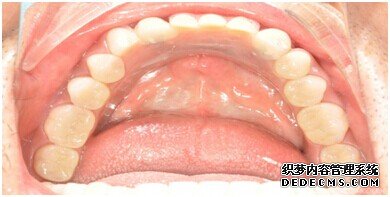

刘女士牙齿拍片初步检查

专家诊断:最后一颗牙齿通常不易清洁,且牙齿长了蛀牙之后也不容易发现,很多人就跟 刘女士一样发现的时候就已经是蛀牙中期甚至是后期了,这个时候一定要尽早治疗。不然和刘女士一样必须拔牙是非常可惜的。

由CT片检查来看,刘女士口腔健康环境还是很好的,牙槽骨也适合种植牙的条件,而且由我们最后一颗牙是非常重要的,经过专家的建议和详细解释了原因之后,刘女士选择了美国百康种植牙。